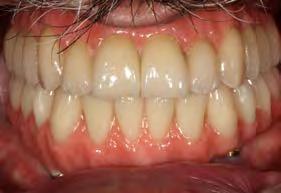

Se presenta una paciente de 13 años 5 meses con el motivo de consulta “es que no me baja el colmillo”. En los estudios extraorales se ve el perfil concavo y labios en contacto durante el reposo (Figura 1). En los estudios intraorales tenemos , clase I esquelética, con crecimiento hipodivergente (Figura 2), clase II molar derecha y clase I molar y canina izquierda, la clase canina derecha no determinada

Figura 1. Perfil, frente en reposo, sonrisa.

(ND), órgano dental (OD) 13 retenido, mordida abierta en sectores laterales, overjet de 3 mm y overbite de 10%, líneas medias dentales desviadas y microdoncia de OD 12 y 22.

Figura 2. Intraorales frente lateral derecha e izquierda. Figura 3. Radiografía panorámica inicial.